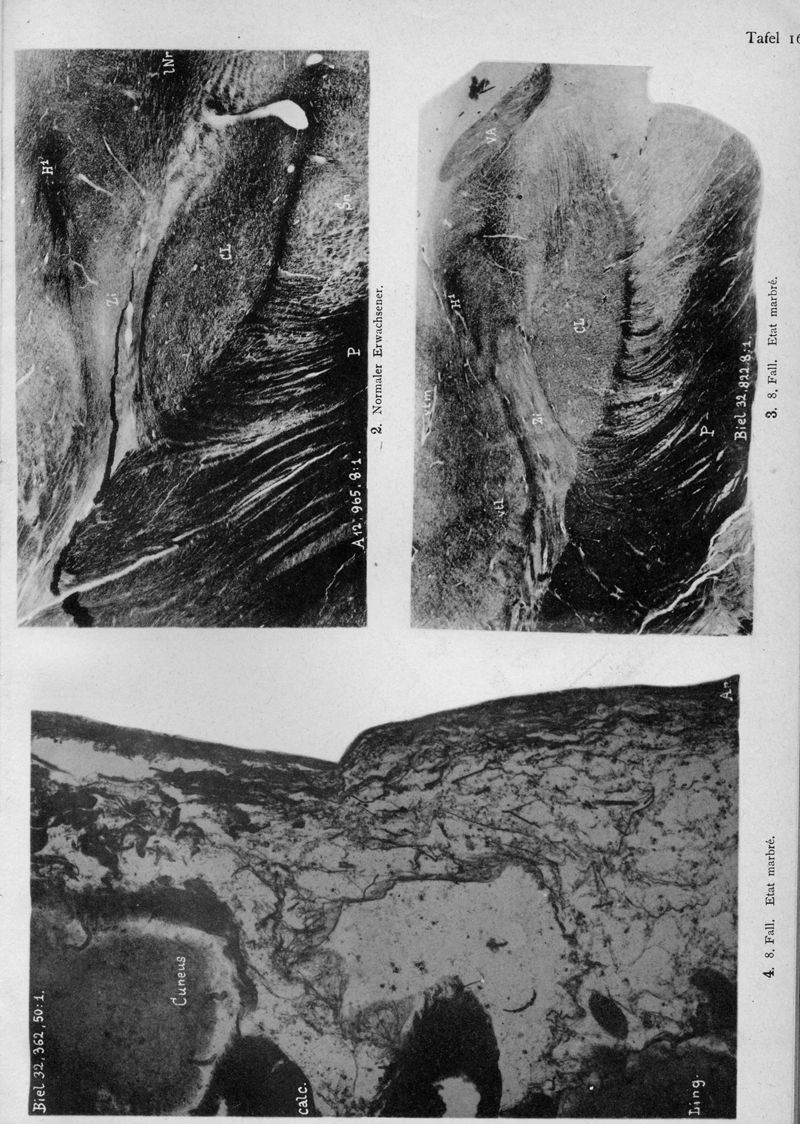

VOGT, Cécile / VOGT, O.

In : Journal für Psychologie und Neurologie,

1920, Vol. 25, pp. 627-846